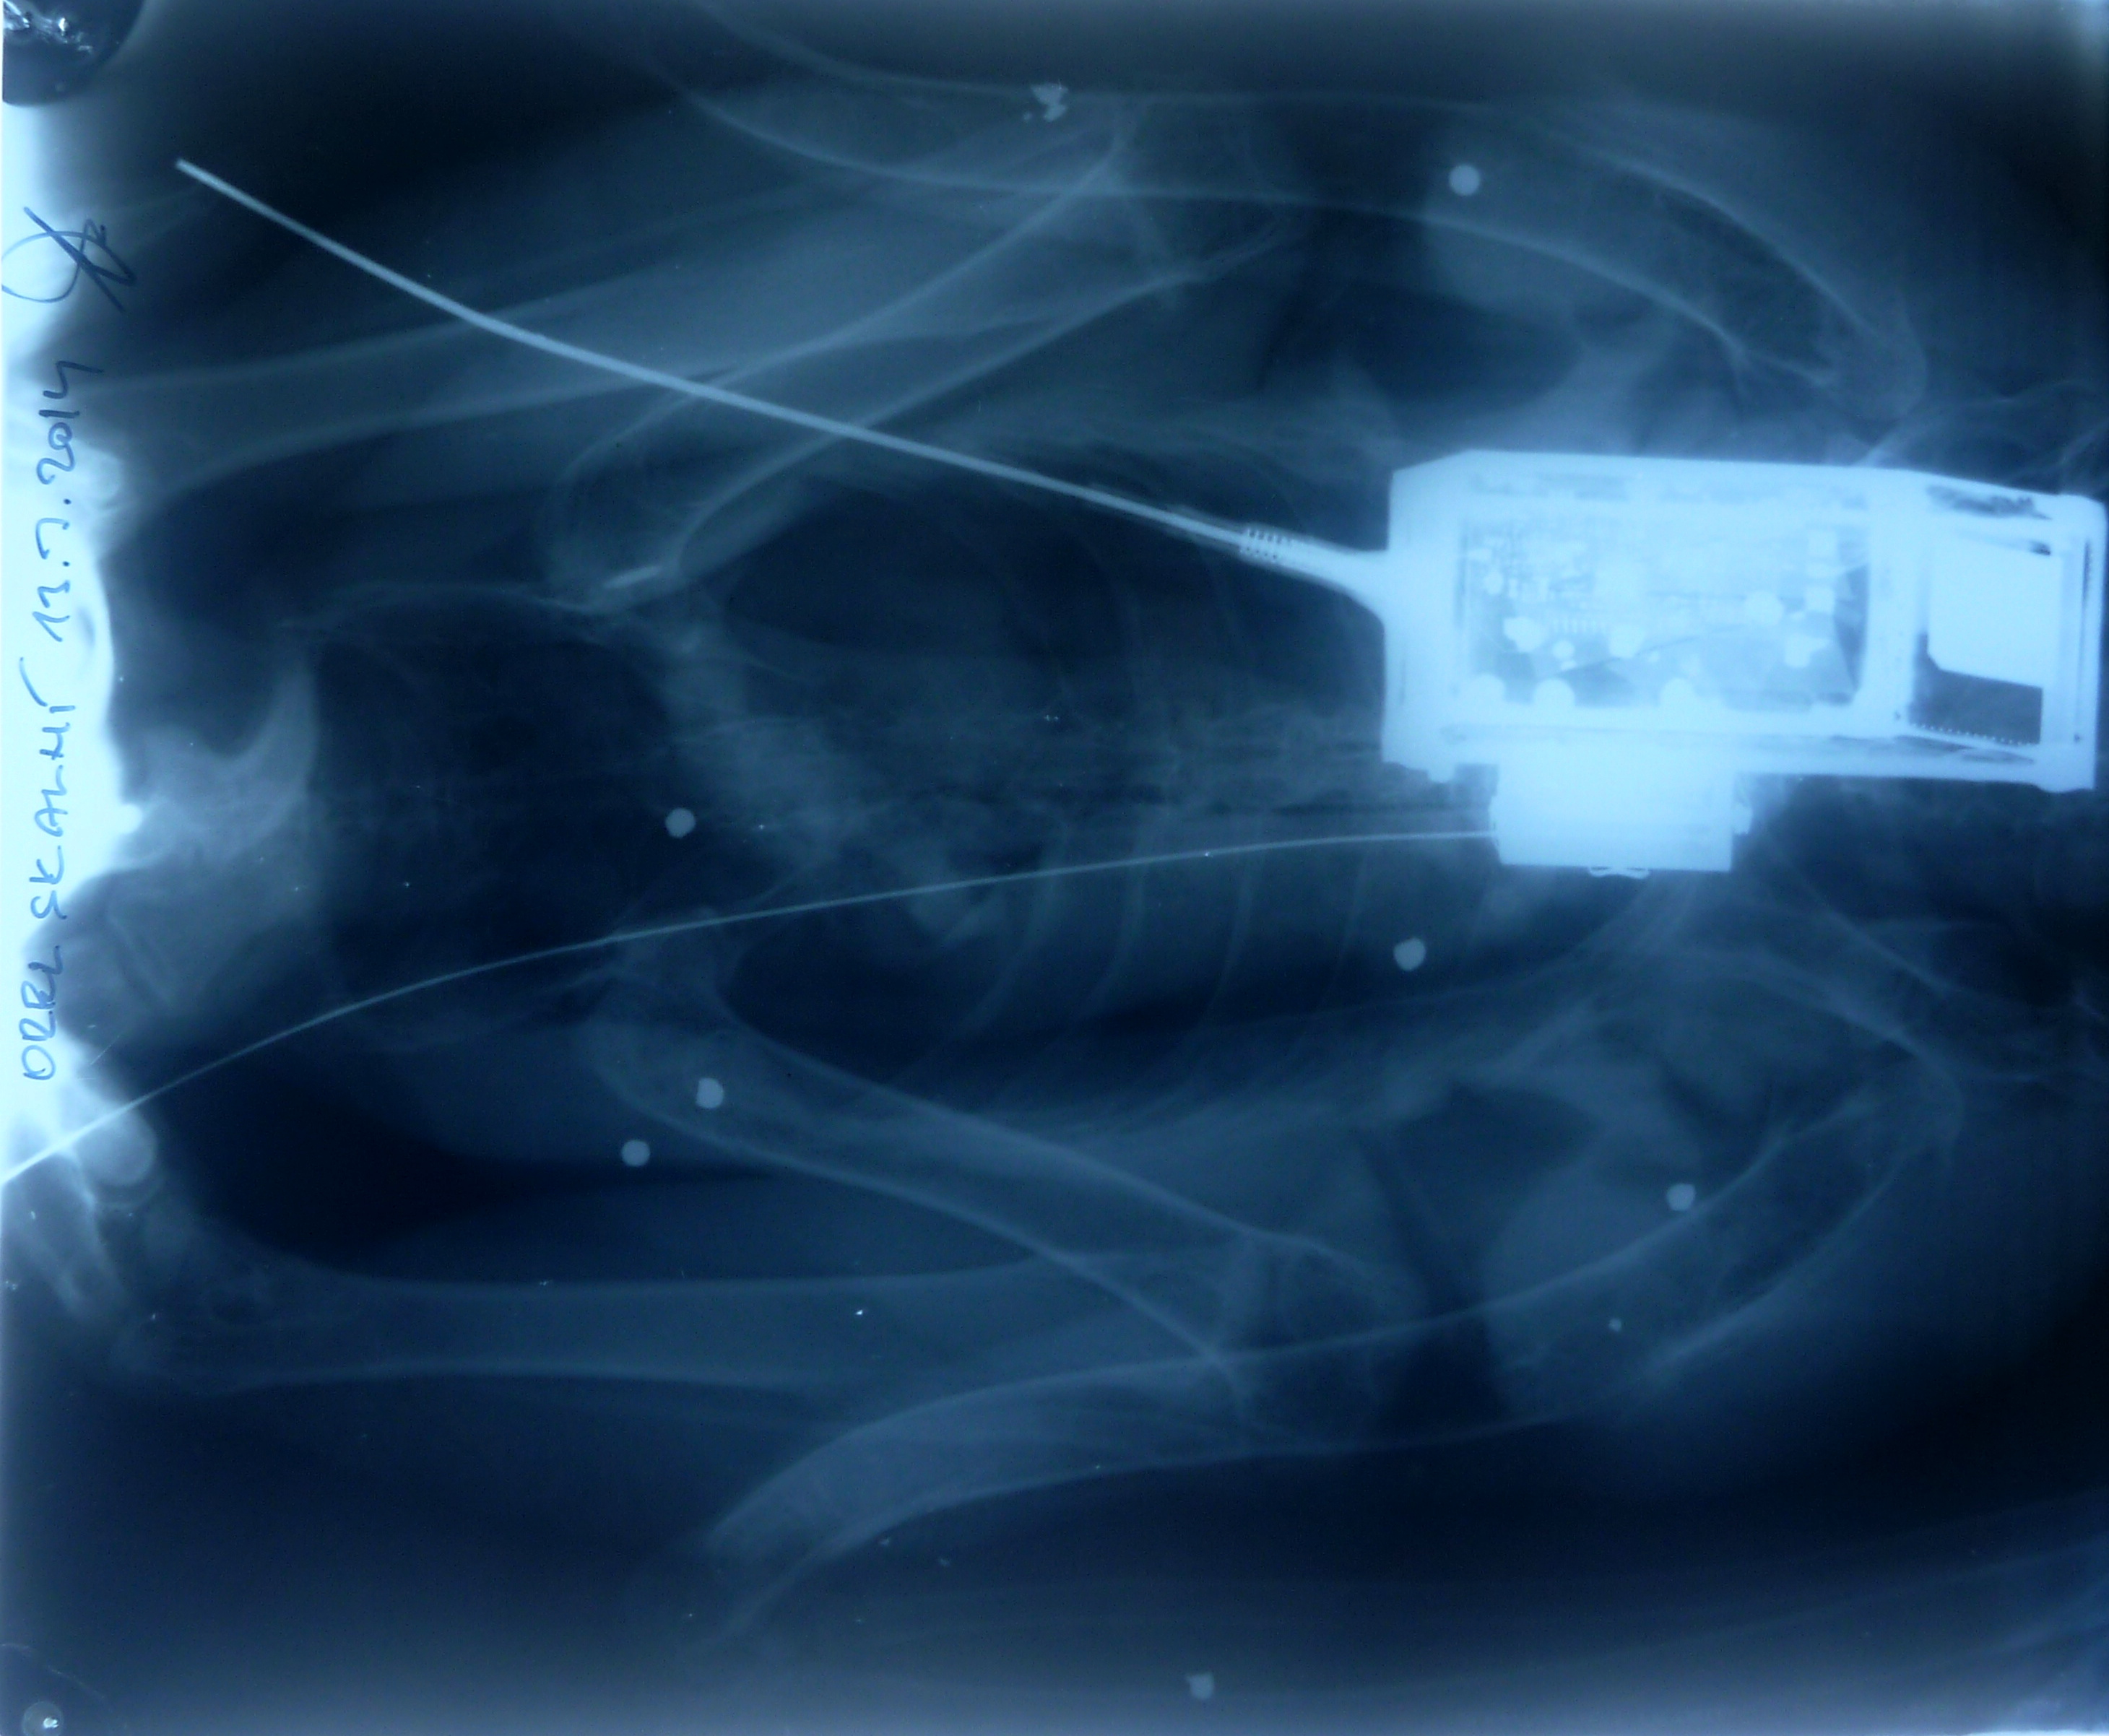

RTG snímky odhalily, že tělo orlice zasáhlo nejméně 11 broků. Vysílačka na jejím těle přestala po

zásahu broky fungovat a možná ji paradoxně zachránila život. Tyto projektily by jinak mohly

vážně poškodit páteř. Zranění vedla k poškození svalové tkáně a některých částí nervového